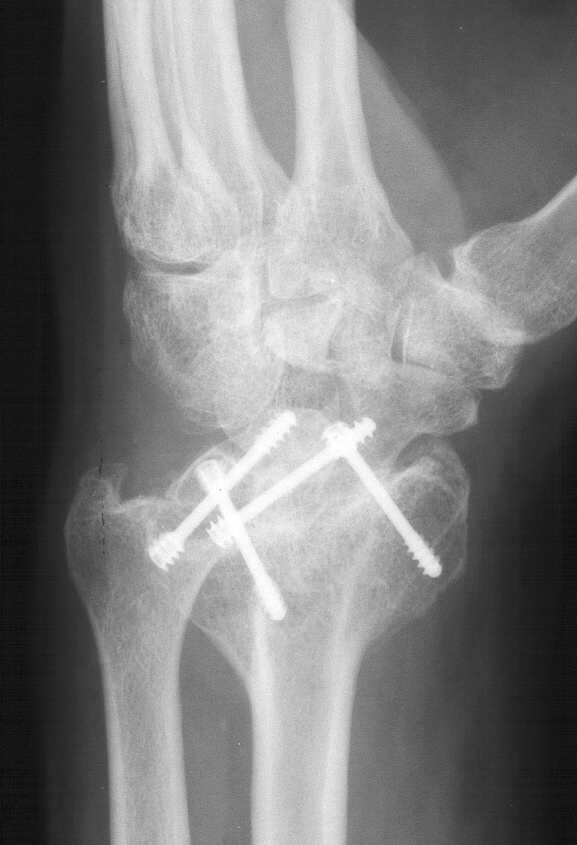

Clinical Example: Radioscapholunate Fusion and Triquetrum excision for Radiocarpal Arthritis

Radioscapholunate fusion is a treatment option for radiocarpal arthritis following distal radius fracture or associated with rheumatoid arthritis. Range of motion is usually less than half of normal following this procedure. Technical modifications to improve range of motion include distal scaphoid excision, or as in this case, triquetrum excision and excision of distal ulnar articular surface to manage ulnolunate abutment. There are a variety of fixation techniques. In this case, crossed Herbert screws were used: dorsal carpal bone to palmar radius and dorsal radius to palmar carpal bone.

Three months postop :